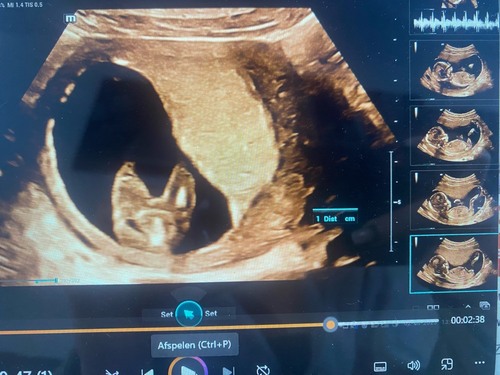

Bij een jongen zijn er testikels met daaraan een penis te zien en bij meisjes is de vagina zichtbaar als kleine drie strepen.

Ik heb nog een foto die hebben ze me via een link gestuurd.misschien is het daarop beter te zien